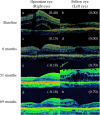

Macular complications such as an epiretinal membrane (ERM), a cystoid macular edema and a macular hole lead to unexpected central vision impairment especially for patients with retinitis pigmentosa (RP). To evaluate the long-term surgical outcomes of pars plana vitrectomy (PPV) for ERM in patients with RP, we retrospectively reviewed the charts of a consecutive series of 10 RP patients who underwent PPV for ERM at Kyushu University Hospital. Visual acuity (VA) testing, a fundus examination, and an optical coherence tomography (OCT) analysis were conducted. The standard PPV using three sclerotomies was performed for ERM. PPV was performed in 12 eyes of 10 patients. One eye was excluded from the outcome assessment due to short period observation (18 months). There was no significantly deleterious change from the baseline to final VA between the operation eyes and the fellow eyes (P = 0.19). Moreover, morphological improvement was obtained in 9 of 11 eyes based on OCT. Our present data suggest that PPV may be tolerable in the management for ERM in RP patients over the long-term. Furthermore, the appearance of the ellipsoid zone was an important factor in the prediction of visual outcome and determination of surgical indication.